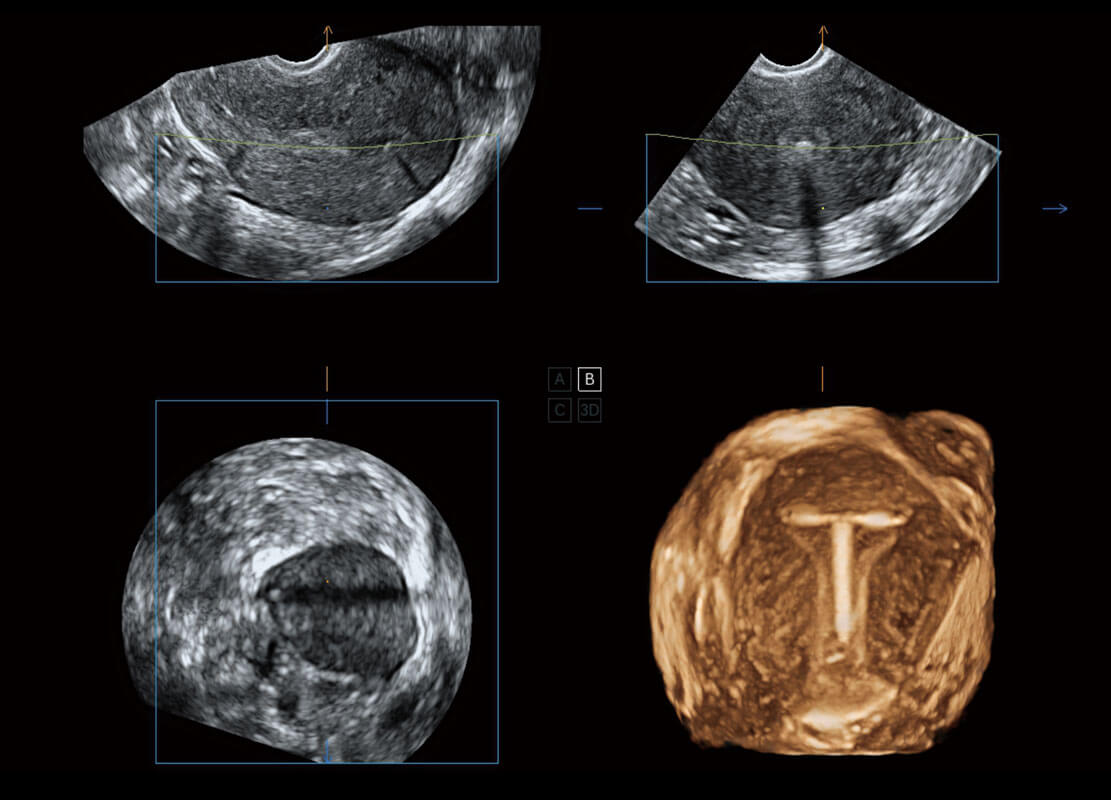

腔內(nèi)三維-宮內(nèi)節(jié)育器

腔內(nèi)三維-光影成像

P60為盆底超聲檢查提供應(yīng)用方案,多種腔內(nèi)及腹部容積探頭提供從二維、三維到四維的優(yōu)異圖像品質(zhì),實(shí)時(shí)快速三維容積數(shù)據(jù)獲取,專(zhuān)業(yè)的測(cè)量工具包等人性化設(shè)計(jì),為超聲醫(yī)生診斷提供有力保障。

Lev.Hiat A-r: 16.33 cm2

Lev.Hiat H-r: 53.70 mm

Lev.Hiat W-r: 43.96 mm

Lt-LUG-r: 24.16 mm

Rt-LUG-r: 19.94 mm

能夠簡(jiǎn)化盆底檢查的操作流程,可在二維模式及三維成像模式下實(shí)現(xiàn)一鍵自動(dòng)提取出標(biāo)準(zhǔn)切面、自動(dòng)識(shí)別當(dāng)前切面、自動(dòng)測(cè)量,提升盆底檢查的高效性,同時(shí)也能讓青年醫(yī)生快捷的獲得準(zhǔn)確的檢查結(jié)果。